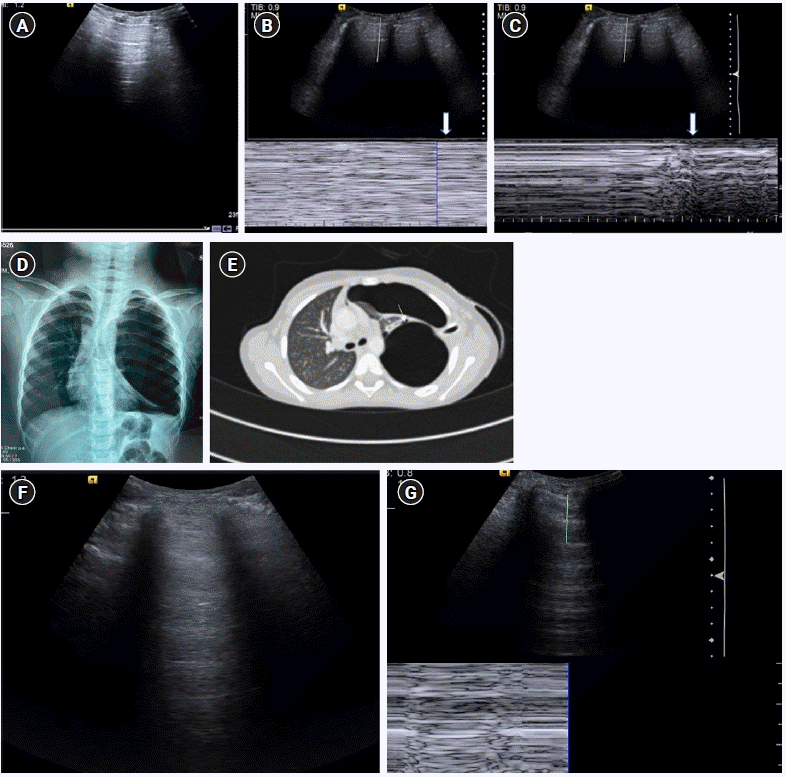

Figure 11.

(A-E) A’ profile. Sagittal grey scale ultrasound scan (A) with M-mode tracing (B) in a 6-year old boy with history of dyspnea, chest pain and previous intercostal chest tube drainage for empyema revealed abolished lung sliding in the form of “stratosphere sign”: horizontal lines above and below the pleural line, in the left anterior and lateral lung zones with presence of A-lines and absent B-lines (known as A’ profile). (C) Diagnosis of pneumothorax was confirmed on ultrasound by localizing the “lung point”: visualizing intermittent stratosphere sign and seashore sign (arrows). The lung point was however visualized in posterolateral lung zones, indicating a large pneumothorax. (D) Chest X-ray in the same patient revealed a large left sided pneumothorax with contralateral tracheomediastinal shift, further confirming the findings of a large pneumothorax as diagnosed on ultrasound. The patient was however hemodynamically stable. (E) Contrast-enhanced chest computed tomography scan chest revealed a bronchopleural fistula (arrow). (F) Cine US clip showing absent lung sliding (Supplementary Material 4). (G) Cine US clip showing “stratosphere sign (Supplementary Material 5).”